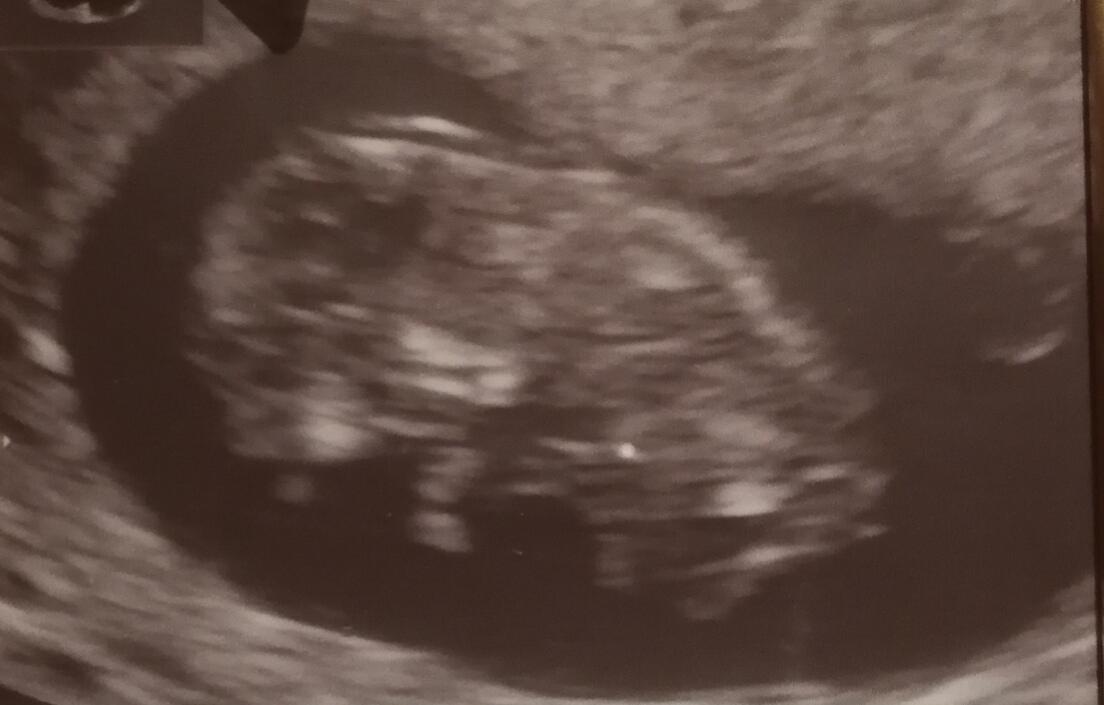

@aneven Ahojky, ja myslim, ze to je zretelna druha carka 🙂 ja mela ted MS po vyvolavanem potratu taky silene nepravidelnou, ale manzel na me poznal, ze jsem tehotna par dni po otehotneni, neverila jsem, udelala jsem si cca za tyden test a bylo tam to stejny, co vidim u tebe a ted uz jsem 11+6 🙂 (UTZ je z 10+2)